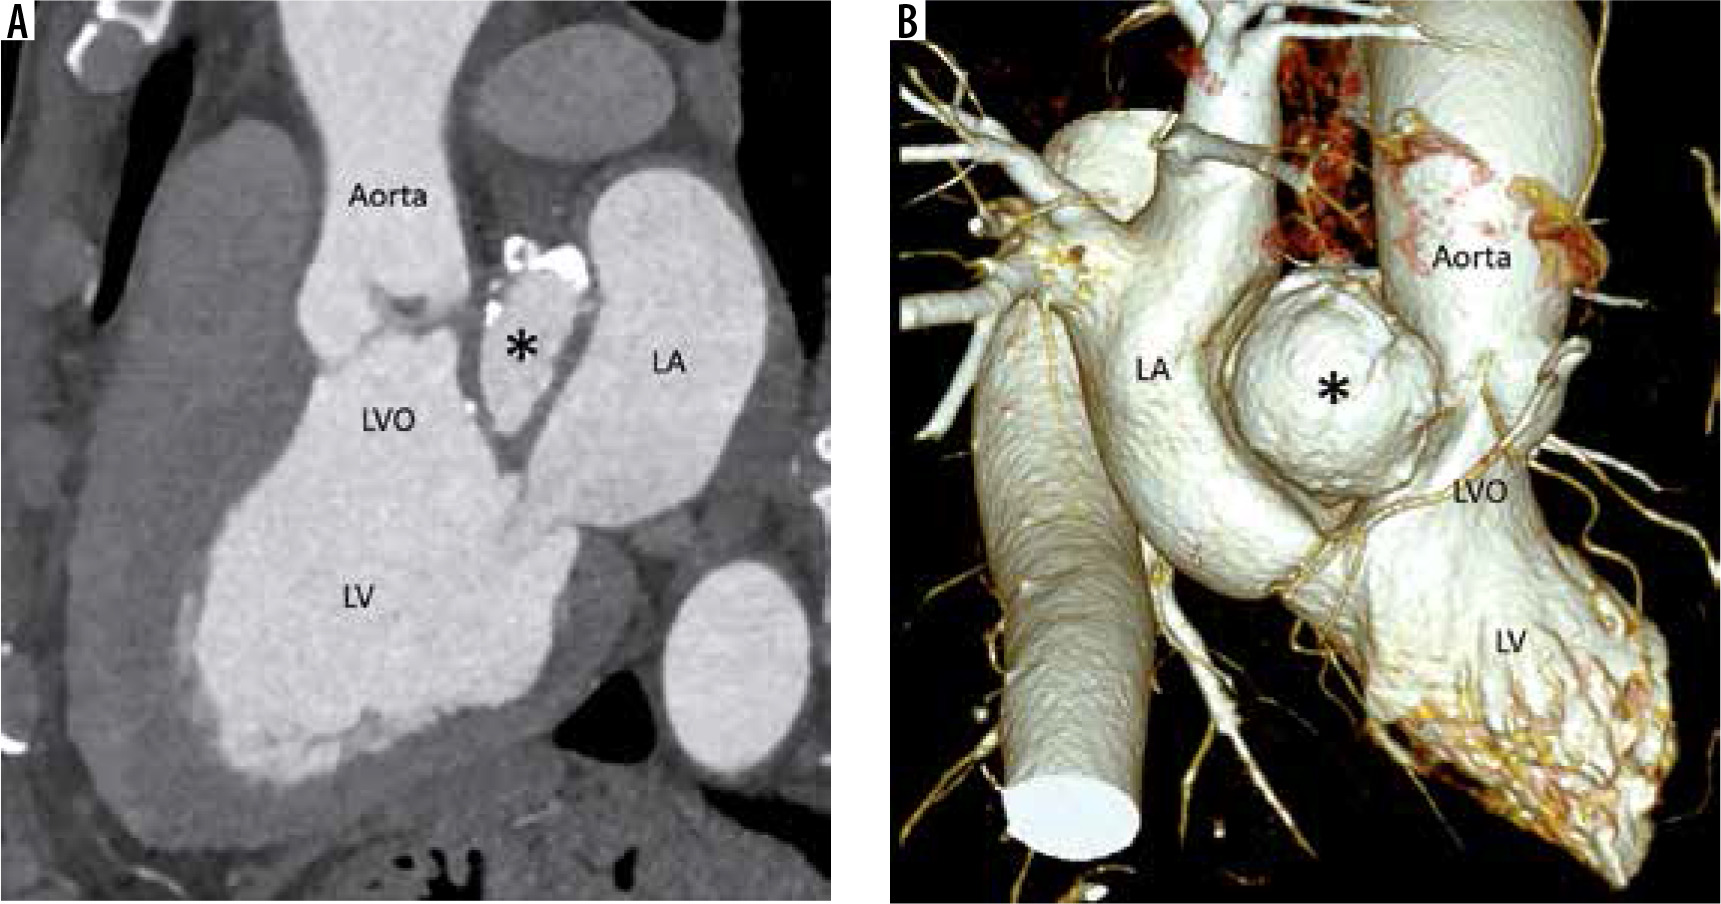

Figure 5

Multiplanar reconstructed image in the oblique sagittal plane (A) and volume-rendered image (B) show a well-defined mitral-aortic intervalvular fibrosa aneurysm (*) with few peripheral specks of calcification. LA – left atrium, LV – left ventricle, LVO – left ventricular outflow